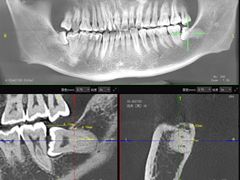

• Dr.Z dental仁康种植矫正中心

• -Dr.Z dental仁康种植矫正中心